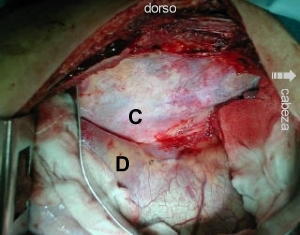

Fotografía B

Toracotomía derecha 10mo. espacio Intercostal, requiere desinserción posterior del diafragma (D), sección del ligamento triangular del pulmón y esposicíon de cuerpos vertebrales T12 a L2

Fotografía C

Identificación espacio vertebral mediante aguja gruesa con comprobación fluoroscópica. ligadura y sección de arterias vertebrales superior e inferior, exposicion cuerpos vertebrales.